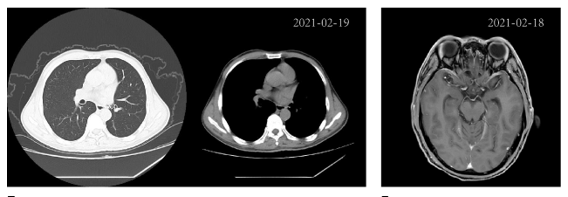

2021年1月-4月,第四次脑脊液NGS检测发现EGFR-SEPT14融合的丰度从7.2%增加到57.0%,同时伴有EGFR扩增(拷贝数6.9)(图2 B)。由于病情恶化和CEA水平不断升高,患者接受鞘内培美曲塞化疗(IP)治疗软脑膜转移,同时奥希替尼进行维持治疗。3个月后,CEA水平从38.42ng/mL下降至12.36 ng/mL,并伴有症状缓解。最后一次CT和MRI扫描,未发现复发或异常(图4)。

图4. 2021年2月肺癌CT及MRI检测结果未发现进展